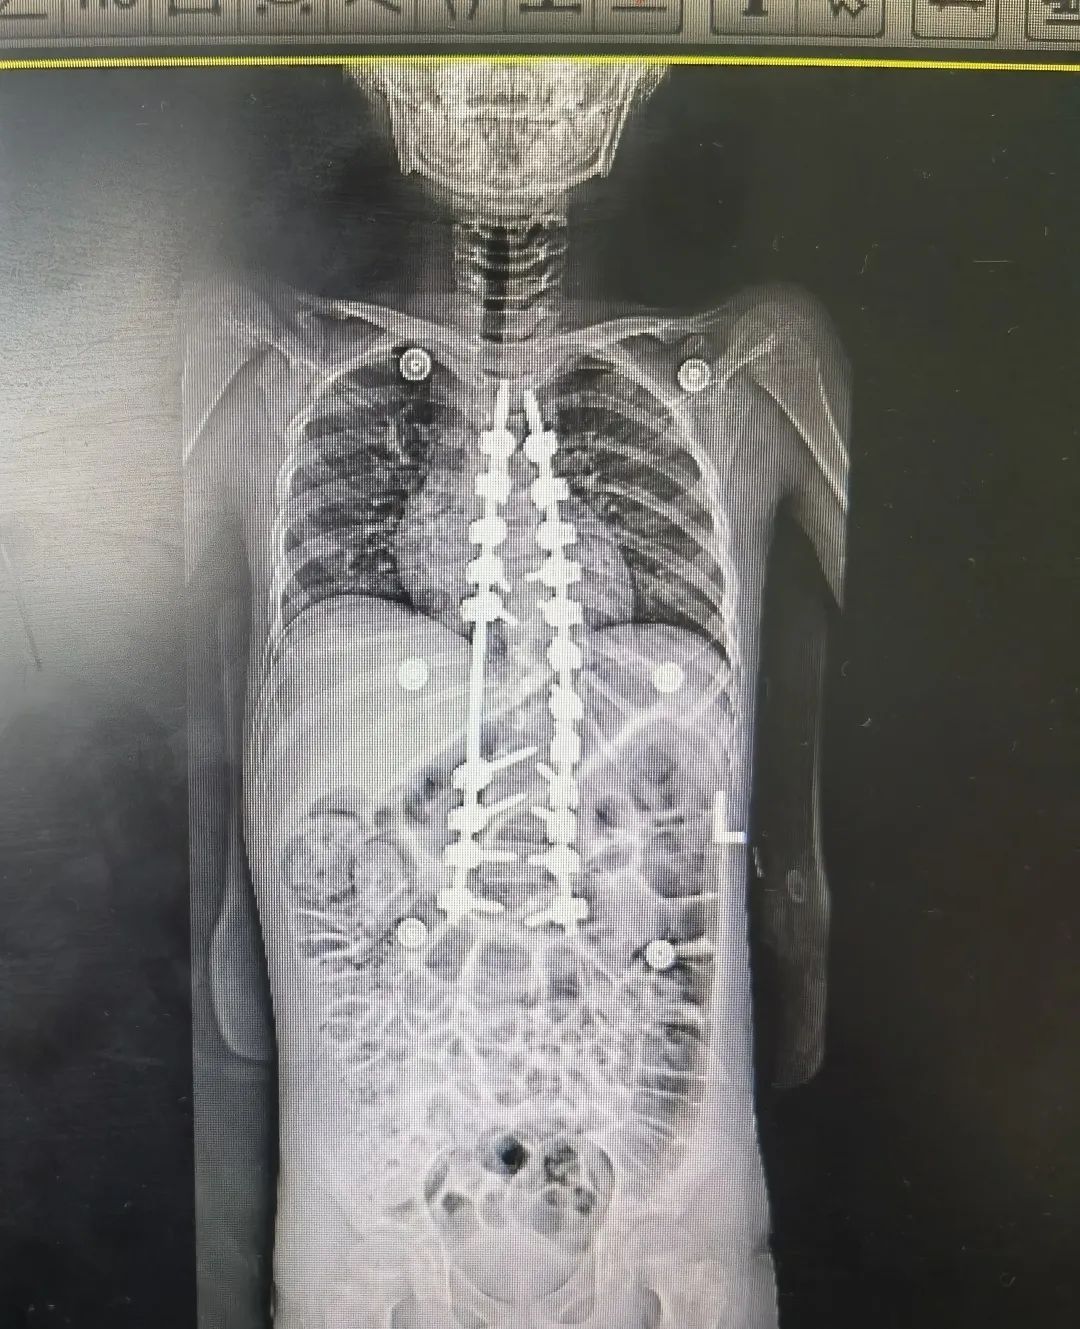

神经肌肉性脊柱侧弯术前术后图

“在这20例的手术里,这个孩子的情况相对特殊,手术难度也比较高。”陈文昊副主任说,“孩子的脊柱侧弯已经达到85°,基本上已经成为一个直角,只能通过手术矫正,如果不手术,这一类型的脊柱侧弯进展会非常快。”

但因为长期生病,玲玲的骨密度非常低,小小年纪已经骨质疏松——她的骨头像70、80岁的老人一样。在弯的最厉害的地方,骨头中根极其纤细,甚至没有,根本打不进钉子。同时神经纤维瘤病的孩子脊髓对矫形的耐受能力较差,为了不影响玲玲的神经和肌力,手术中陈文昊副主任只能降低矫形强度。

克服种种不利因素,手术基本达到了既定的矫正效果,命运坎坷的玲玲在日后也能像其他孩子一样抬头挺胸。